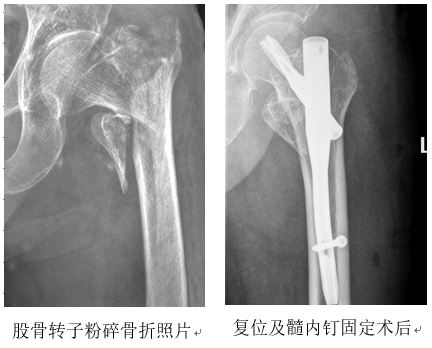

体查:神清,被动卧位,左下肢短缩,左髋外侧有瘀斑、肿胀、压痛,有纵轴叩击痛,左髋不能活动。X线照片示左股骨转子粉碎骨折,远端向外、上移位。

考虑到患者以往生活能够自理,为了提高生存质量、避免长时间卧床带来的并发症,建议实施微创手术——骨折手法复位、髓内钉固定。面对超高龄和糖尿病、贫血、低蛋白血症等基础疾病,医师进行了全面检查和细致分析,经多个相关科室会诊后,为其制定了全面的手术及围手术期治疗方案。经过1周的精心治疗和护理,老人的身体状况明显改善。随后,在全麻下为患者实施了骨折复位、髓内钉(PFNA)内固定术:骨折经牵引架牵引、手法复位后透视见对位良好,再行穿钉髓内固定,手术3个切口全长不超过10厘米,出血量少于100毫升,手术过程顺利。术中透视和术后照片显示,骨折复位和内固定情况良好。